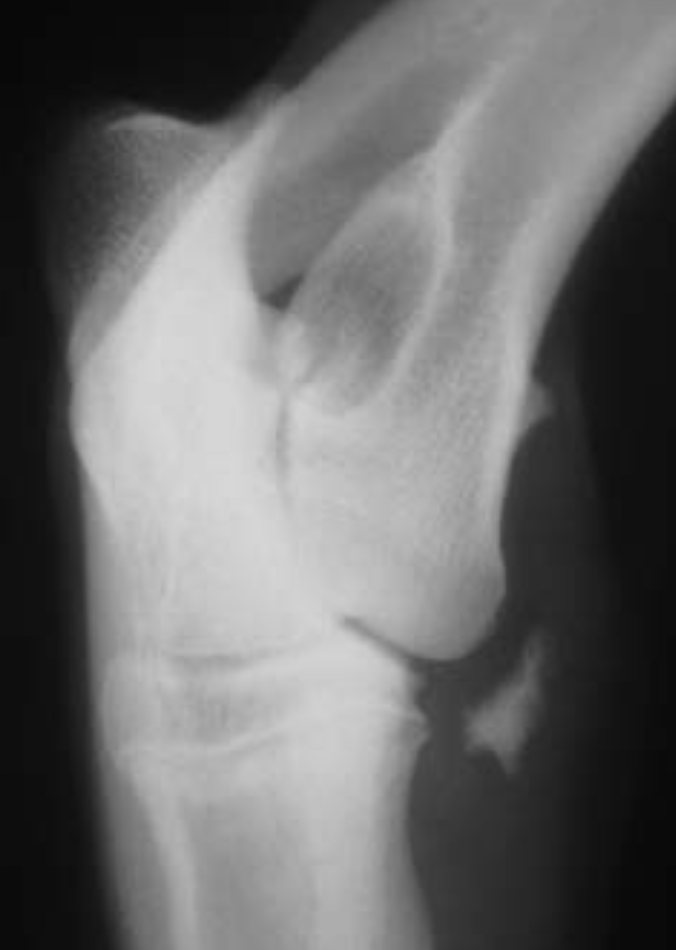

Q

3.5m Yorkie

A

lateral humeral condylar fracture - see its caudal displacement, superimposed over the cranial ulna.